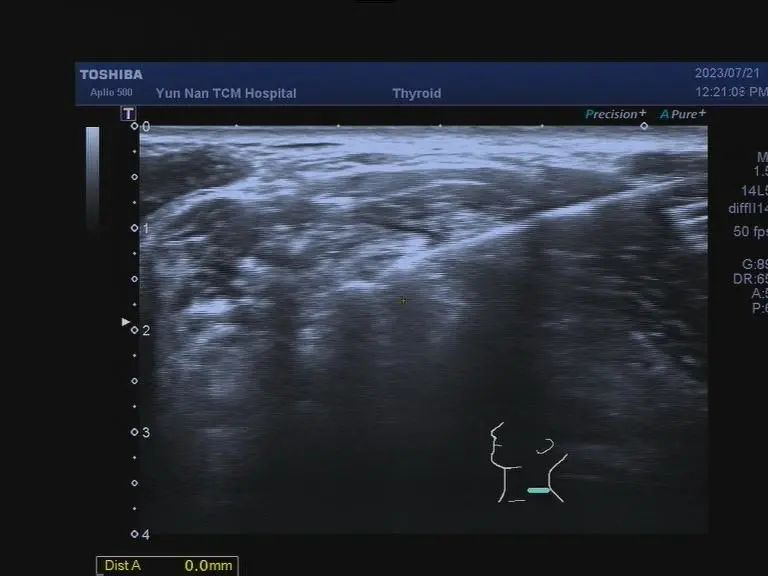

超声引导下行肺脓肿穿刺术

1.超声介入穿刺活检:如淋巴结、乳腺肿块、皮下和肌肉层内肿块等的活检、甲状腺细针穿刺活检、肾活检等,穿刺活检是获取病理诊断的微创方法,相对于手术切开取材,具有操作时间短,取材准确的优势;

2.超声介入置管引流和药物注射治疗:如肺脓肿的引流、胸腔、腹腔积液的引流、心包腔积液的引流以及PTCD术等;